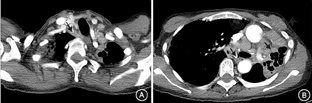

入院查体:身高163 cm,体重39.5 kg,血压113/68 mmHg(1 mmHg=0.133 kPa),营养差,全身毛发及皮肤色素大面积脱失。双肺呼吸运动对称,左侧语颤增强、呼吸音减弱,右上肺少量细湿啰音,未及胸膜摩擦音。心、腹查体(-)。双上肢近端肌力4级,远端肌力5级。双下肢近端肌力5级,双足背屈4级,跖屈5级,余神经系统查体未见明显异常。入院后完善相关检查:血常规未见明显异常;尿常规:微量尿蛋白;血生化:肝功能正常,血肌酐205 μmol/L,血钙3.47 mmol/L(正常参考值:2.13~2.70 mmol/L);红细胞沉降率49 mm/h,超敏C反应蛋白24.55 mg/L;结核菌素(PPD)试验(-),血结核感染特异性T细胞检测(T-spot.TB)(-);免疫指标:抗核抗体:抗Ro 52抗体(+++),抗可提取性核抗原抗体、抗中性粒细胞胞质抗体阴性,补体正常。患者血钙升高,行钙磷代谢检验:游离钙1.64 mmol/L,24 h尿钙9.07 mmol,血磷1.06 mmol/L,1,25二羟维生素D3 278.4 pmol/L,25羟维生素D 88.8 nmol/L,甲状旁腺素4.9 ng/L。肾脏病变评估:血尿素氮14.0 mmol/L,血尿酸571 μmol/L,24 h尿总蛋白定量0.66 g,尿蛋白电泳示肾小管性蛋白86%,尿免疫固定电泳(-);肾脏超声示双肾集合系统内多发结石,左肾囊肿伴壁钙化。肌肉病变评估:肌酶谱:天冬氨酸转氨酶38 U/L,乳酸脱氢酶252 U/L,CK 133 U/L;肌电图示肌源性损害,RNS未见异常;肌肉活检病理示多发灶性肌纤维坏死,肌内膜及束膜散在CD4+和CD68+细胞,炎性病灶内以CD4+细胞为主,夹杂CD8+和CD68+细胞及个别CD20+细胞。肿瘤标志物:血清蛋白电泳未见M蛋白,鳞状细胞癌抗原、神经元特异性烯醇化酶、细胞角蛋白19、胃泌素释放肽前体、癌抗原199、癌抗原125均轻度升高;胸部增强CT(图1):左肺体积减小,上叶毁损肺,纵隔左移;双肺散在结节影,两肺门及纵隔多发肿大淋巴结;双侧胸膜增厚。全身骨显像:全身骨骼摄取增高,颅骨为著,不除外代谢性骨病所致。骨密度:未见明显异常。单光子发射计算机断层成像(SPECT)/CT融合显像:前上纵隔、隆突下多发放射性摄取增高团块及结节,恶性肿瘤可能。行支气管镜检查,双侧支气管肺泡灌洗液(BALF)抗酸染色、结核/非结核分枝杆菌核酸测定等病原学检查均阴性,未见瘤细胞。行CT引导下前上纵隔占位穿刺活检术,病理检查结果示:纤维脂肪组织显慢性炎,可见上皮样肉芽肿及多核巨细胞反应,符合肉芽肿性疾病,未见干酪样坏死(图2);特染结果:六胺银(-),抗酸-TB(-),弱抗酸染色(-),考虑结节病。血管紧张素转化酶(ACE)137 U/L(正常参考值:12~68 U/L)。最终诊断:结节病、陈旧性肺结核。

注:A.纵隔肿物(↑),可见纵隔多发小淋巴结,纵隔及气管左移;B.左肺纵隔左移,双侧肺门、气管隆突下可见多发肿大淋巴结(↑)